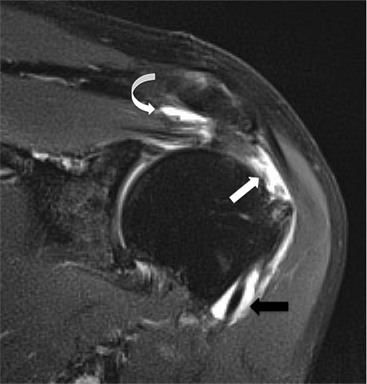

The primary sign of a rotator cuff FTT is a focal deficiency of the tendon (Figs. 46-4 and 46-5). This nearly always occurs at the tendon insertion on the tuberosity. The margins of the tear are best delineated when there is fluid within the tendon defect. Secondary signs of an FTT include the presence of fluid in both the GHJ and SAB, and flattening or concavity of the subacromial fat plane.

PTTs are less reliably demonstrated by both MRI and US, and it may be difficult to differentiate tendinopathy from partial tears. Focal clefts, tears, or tendon thinning affecting the articular margin of the footprint of the tuberosity are most common (Figs. 46-6 and 46-7). Tendon thickening is not always present. It is important not to mistake magic angle phenomenon on short TE MR sequences or anisotropy on US as evidence of tendinopathy.2